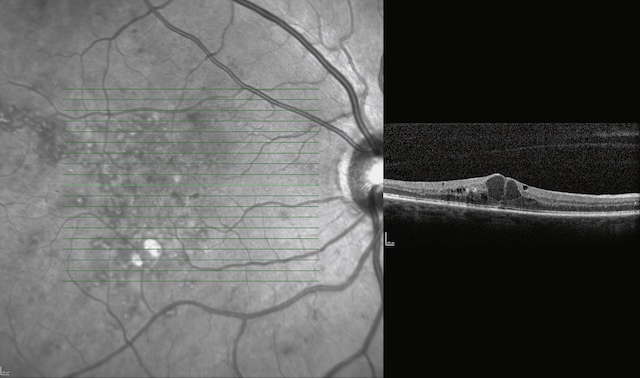

- • un œdème maculaire qui se traduit par un épaississement de la rétine maculaire détectable en OCT. L’œdème est dit cystoïde (œdème maculaire cystoïde [OMC]) lorsqu’il existe un épaississement microkystique de la rétine maculaire (fig. 20.12);

Fig. 20.12 œdème maculaire cystoïde sévère.

A. En angiographie à la fluorescéine, accumulation de colorant dans des logettes cystoïdes étendues à toute la surface de la macula. B. L’OCT montre l’épaississement microkystique rétinien maculaire.L’image A présente une angiographie à la fluorescéine montrant une hyperfluorescence diffuse et intense centrée sur la macula, avec des dépôts lipidiques visibles en couronne évoquant une perméabilité vasculaire marquée. Des microanévrismes et de fins vaisseaux fuyants structurent un tableau typique d’œdème maculaire cystoïde sévère. L’image B, en coupe OCT, confirme cet aspect avec plusieurs cavités hyporéflectives intrarétiniennes bien délimitées, traduisant un œdème organisé. L’architecture fovéale est altérée, mais le contour rétinien reste intact, sans traction évidente. L’épaississement rétinien est net, confirmant un stade avancé de la pathologie.